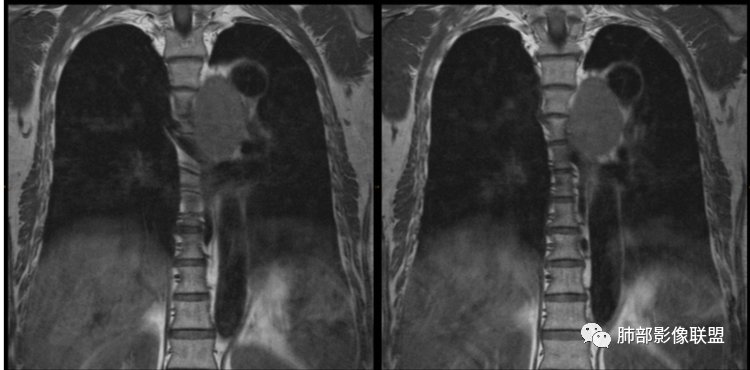

患者,男,43岁,无意间发现纵隔肿物,无胸闷胸痛,无心慌气短,无咳嗽,无吞咽困难等不适。体检发现的,无症状。

气管、左主支气管后方,食道左侧囊性占位,壁薄且均匀、光滑。气管及左主支气管受压凹陷、变形。

食道也受压变形、移位。

MR所见也差不多。